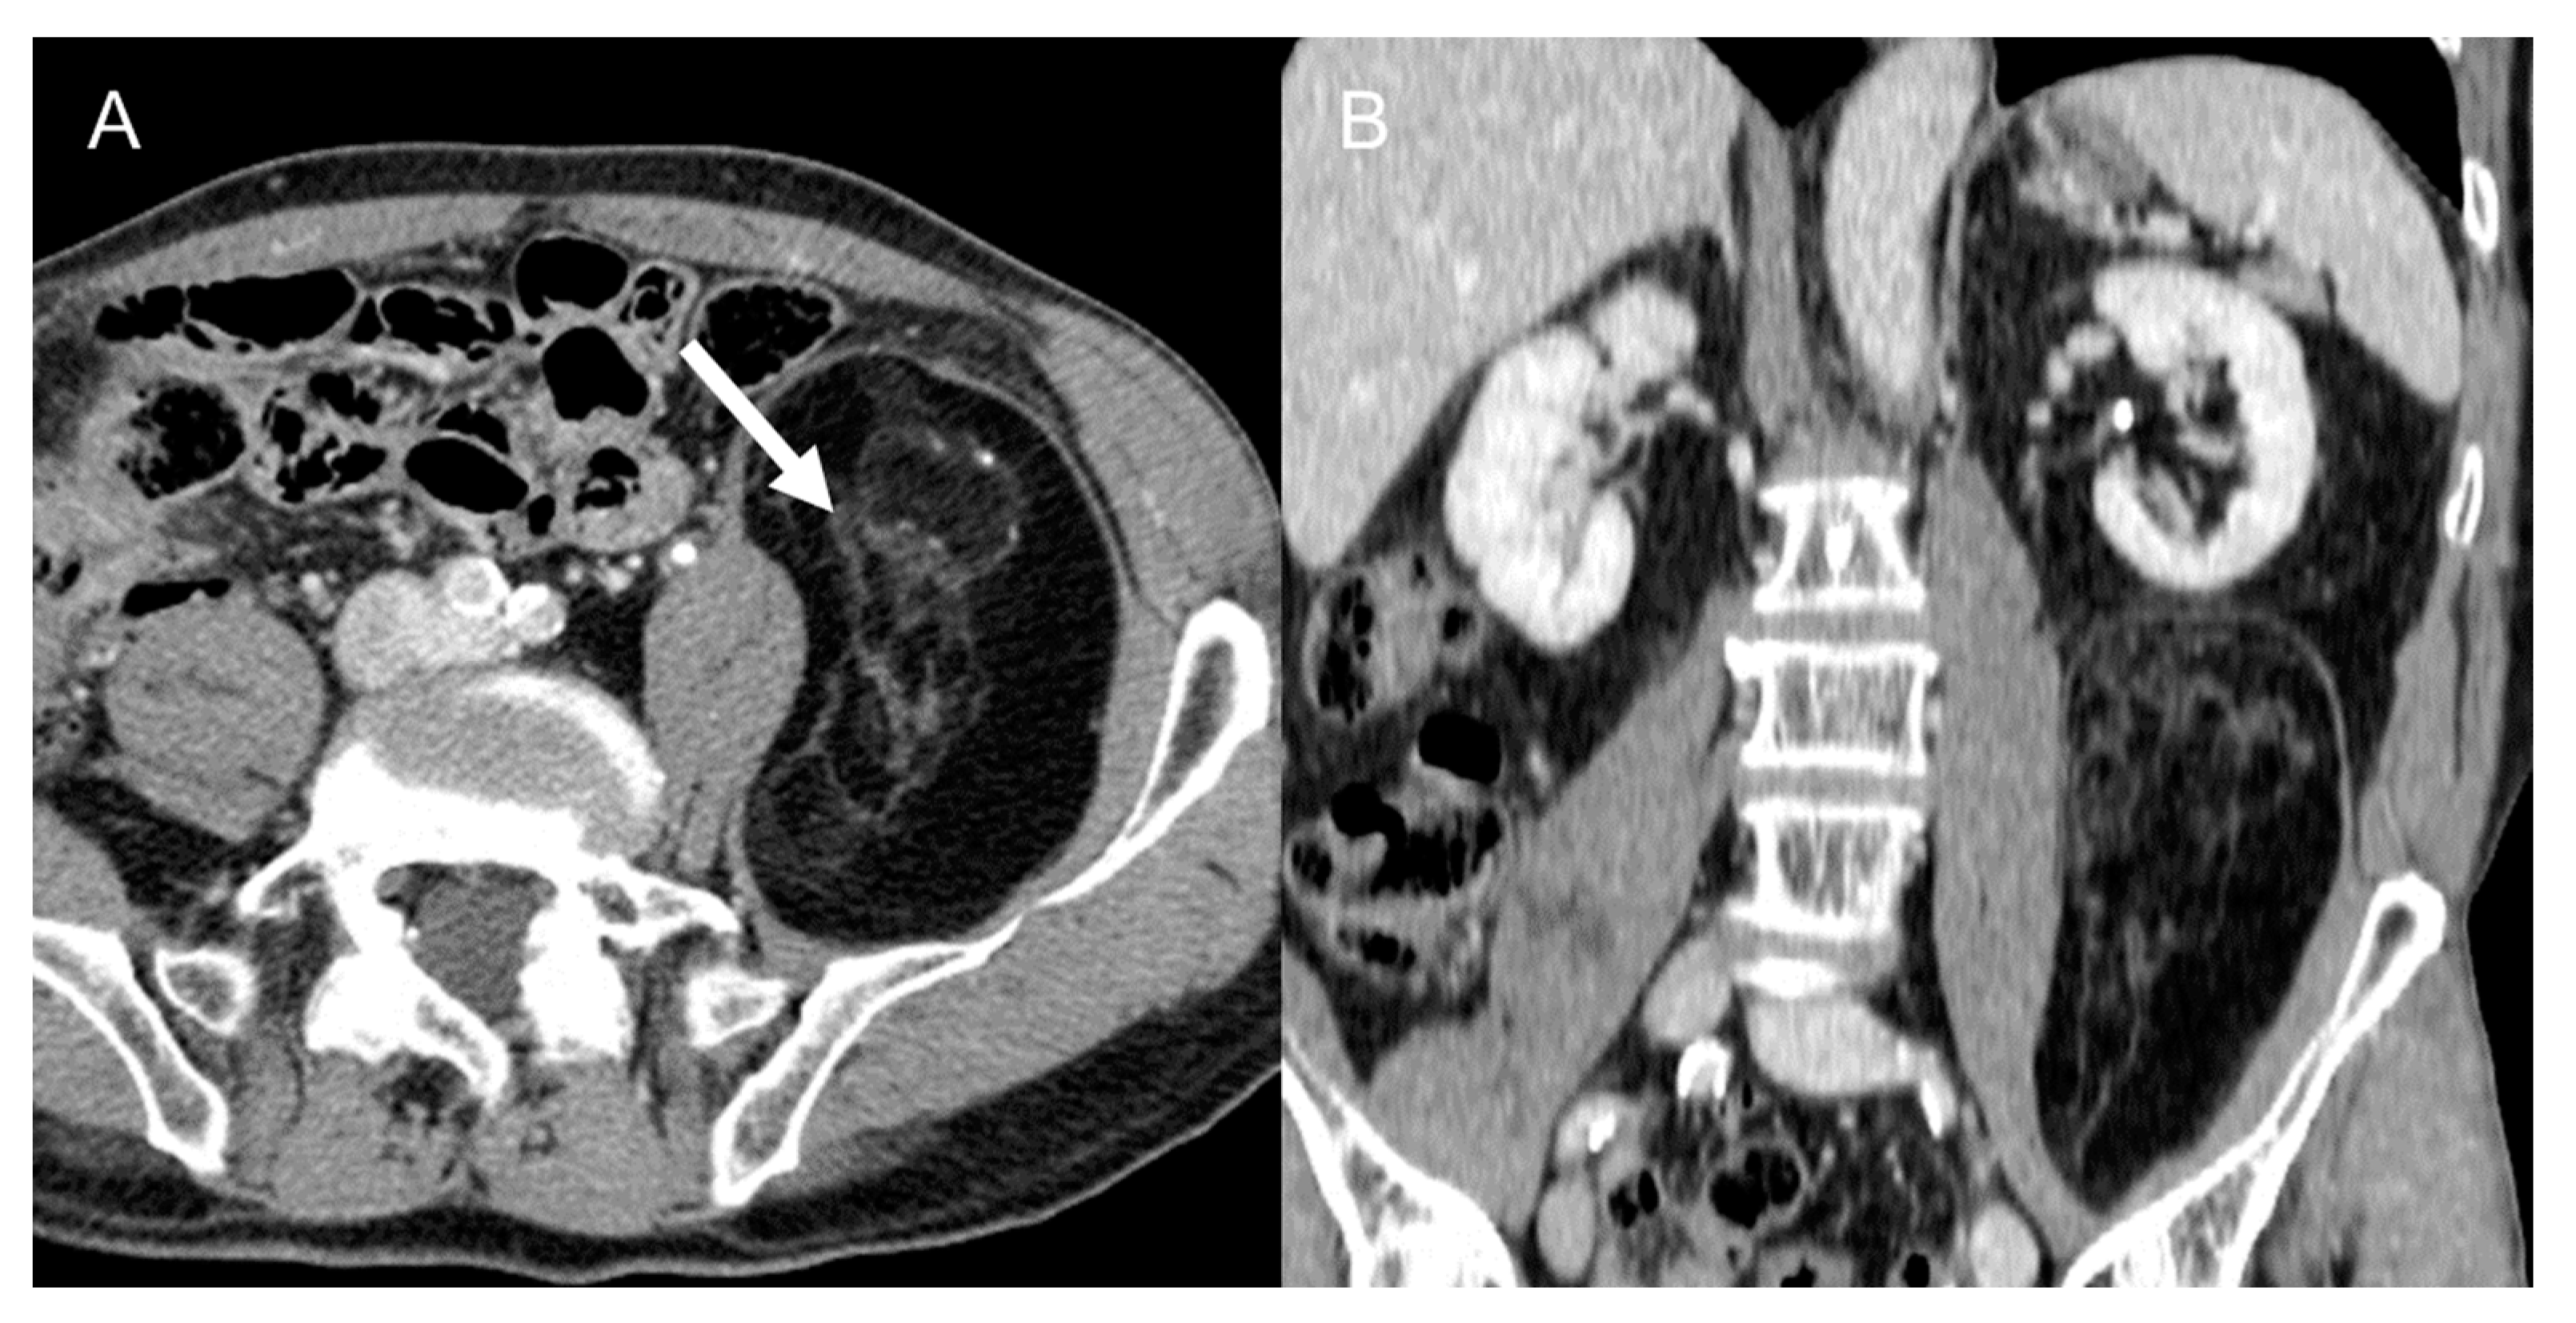

- Dedifferentiated liposarcomas (Figure 2) are high-grade tumors with poor prognosis. Characteristic features include heterogeneous nonlipomatous mass within, adjacent to, or surrounding a fatty mass [37,38]. There may be no evidence of fat-density tissue in up to 20% of cases, making the imaging diagnosis difficult [40]. Enhancing septa within the fatty portions are frequently seen [37]. Calcifications are rare (around 25% of cases) and are poor prognostic factors [39].

Figure 2. Dedifferentiated retroperitoneal liposarcoma in a 68-year-old man. Axial (A) and coronal (B) contrast-enhanced CT images in the venous phases show a 24 cm solid mass in the right retroperitoneal space, with internal necrotic areas and adjacent nodules (arrows). The lesion was histologically confirmed at biopsy.